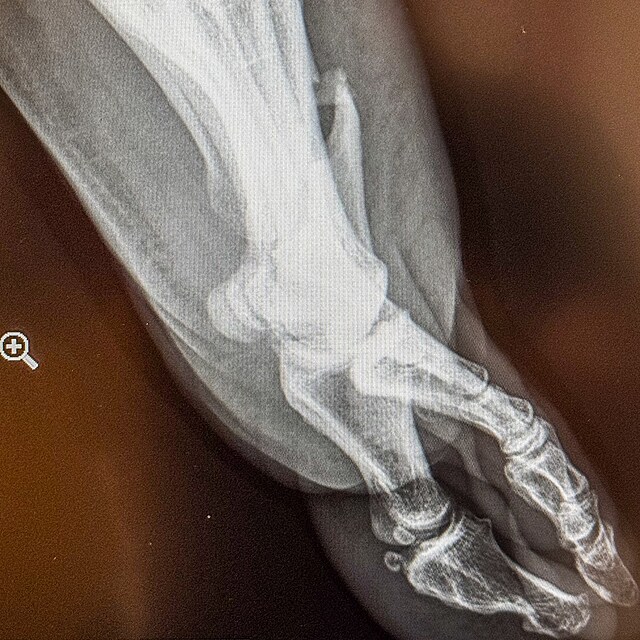

Podle jeho příspěvku na Facebooku to vypadá, že do něj najel vůz Martina Šoltyse, před kterým se podnikatel pokoušel schovat za skálu, bylo mu to nicméně málo platné. Kámen se rozlomil a vážně Cíglerovi poranil nohu.